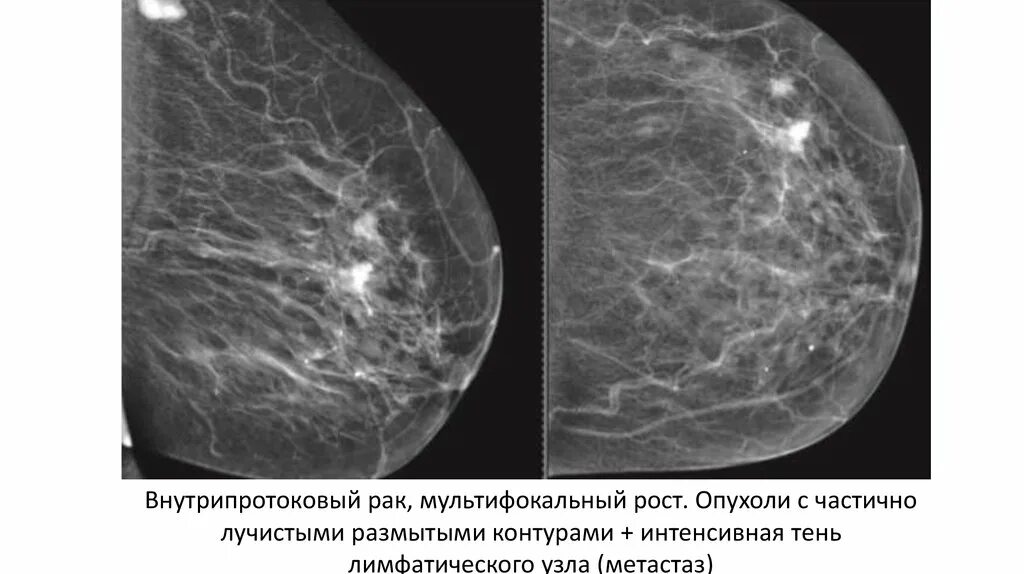

Метастазы в лимфоузлах молочной железы